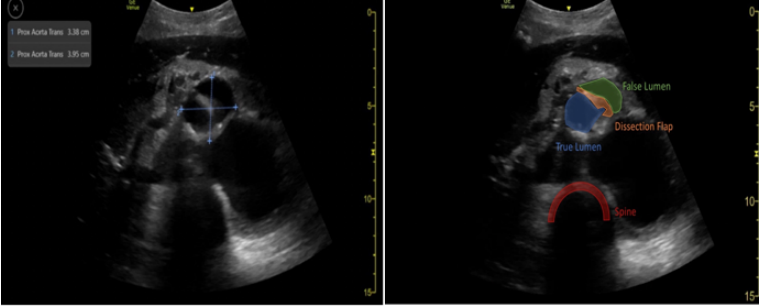

对于以呼吸困难为表现的急性呼吸衰竭患者,可以通过BLUE方案鉴别病因;对于休克患者,可以通过RUSH方案快速鉴别;对于心跳骤停患者,可以通过FEEL流程进行筛查。通过这些流程化的筛查基本上可以判断患者是否具有ECMO指征,同时筛查出部分可能快速解除的病因(如心包填塞、气胸、大量胸腔积液等)进行及时处理,从而避免不必要的ECMO治疗。此外,还可以排查一些VA-ECMO的禁忌证,例如主动脉夹层、主动脉瓣重度关闭不全。如下所示为急性呼吸衰竭、严重二尖瓣狭窄患者,此类患者不需VV-ECMO。对于心源性休克患者,经过超声评估发现是主动脉夹层(图1),这是VA-ECMO的禁忌证。

图1  主动脉夹层患者超声表现